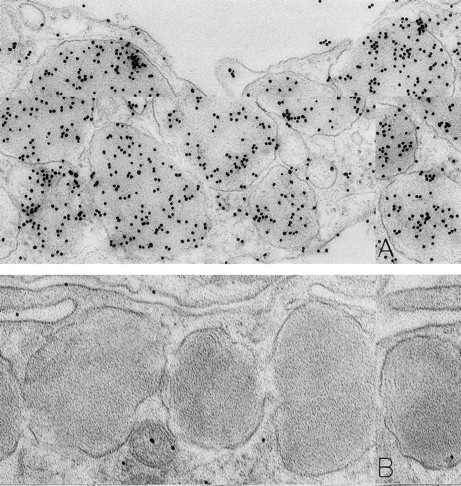

A skin biopsy from an rhSCF-injected test site (obtained 1 hour 40 minutes after the SC injection of 25 μg/kg of rhSCF ) from patient no. 3, who had received a single dose of rhSCF (day 1 of dosing), shows extensive DAO-gold-labeled fibrin (A) that is not seen if the section was digested with DAO before staining with DAO-gold (B). Original magnifications: (A) ×56,000; and (B) ×52,000.

The rhSCF-injected skin sites had extensive deposits of extracellular fibrin. Much of this fibrin was bound to interstitial collagen, whereas some fibrin deposits occurred near secretory mast cells and their extruded granules. There was striking labeling of these masses of interstitial fibrin with DAO-gold (Figs 2D and 4A). By contrast, no fibrin was detectable in the control skin biopsies. Specificity controls for the enzyme-affinity method for histamine resulted in no labeling of fibrin (Fig 4B). Bundles of extracellular interstitial collagen in rhSCF-injected sites also stained with the DAO-gold reagent (Fig 5A). Again, specificity controls resulted in no labeling of the collagen at such sites (Fig 4B). In many areas, secretory mast cells, with DAO-gold-negative, extruded, membrane-free granules attached to their surfaces, were intimately associated with gold-labeled collagen fibrils (Fig 2A). However, collagen in the basal lamina (whether present beneath the basal layer of the epidermis and skin adnexae, surrounding Schwann cells in dermal nerves, or underlying vascular endothelial cells and pericytes) did not stain with the DAO-gold enzyme-affinity method (data not shown).